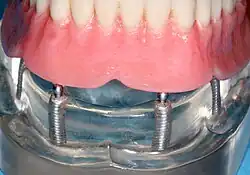

- имплантация All-on-4 («все на 4») — это зубопротезирование полного зубного ряда методом имплантации четырёх искусственных корней (имплантатов) в костную ткань челюсти пациента с последующей установкой на них протеза.

- создать опору для улучшения фиксации съёмного протеза;